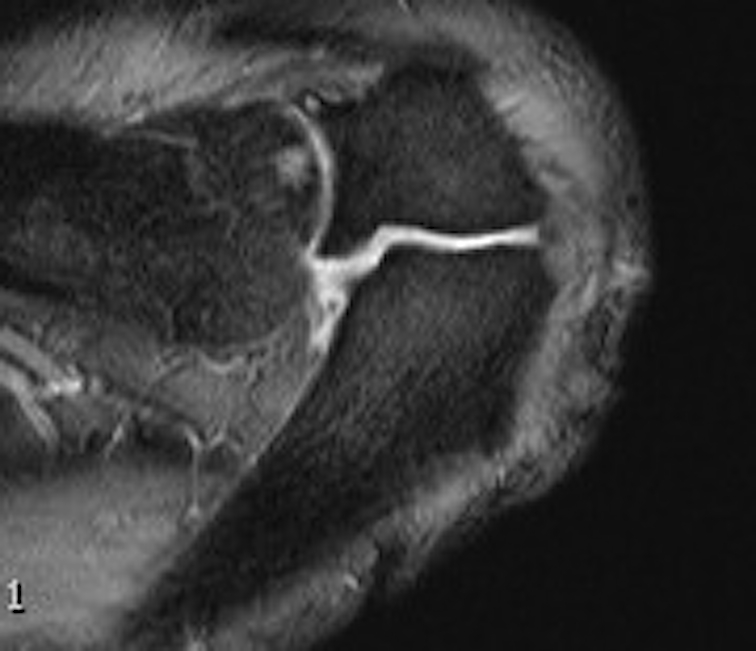

MRI

Useful investigation - may show edema if problematic / mobile / causing pain

Axial MRI with meso-acromiale

Axial MRI Sagittal MRI